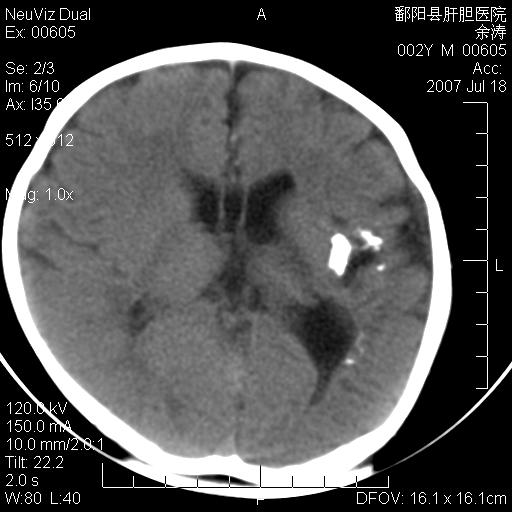

男性 2岁:平时智力障碍。外伤后行颅脑平扫。

左颞叶“萎缩”,可见不规则高密度影,并左侧室扩大,呈负占位效应...支持考虑先天发育异常(血管发育畸形)可能性大,建议结合进一步检查了解。

左颞叶“萎缩”其内可见不规则点条状高密度影,并左侧室扩大,考虑颅面血管瘤病

脑裂畸形;左侧脑脑萎缩;透明隔囊肿;血管畸形?

开唇型脑裂畸形

左侧颞顶叶钙化灶,其内有小片状低密度影 边缘清晰。与之相邻的脑沟增宽增深 ,左侧侧脑室体部牵拉扩大。考虑左颞顶软化灶并局限性脑萎缩。透明隔间腔。

该病人应该还有胼胝体发育不全